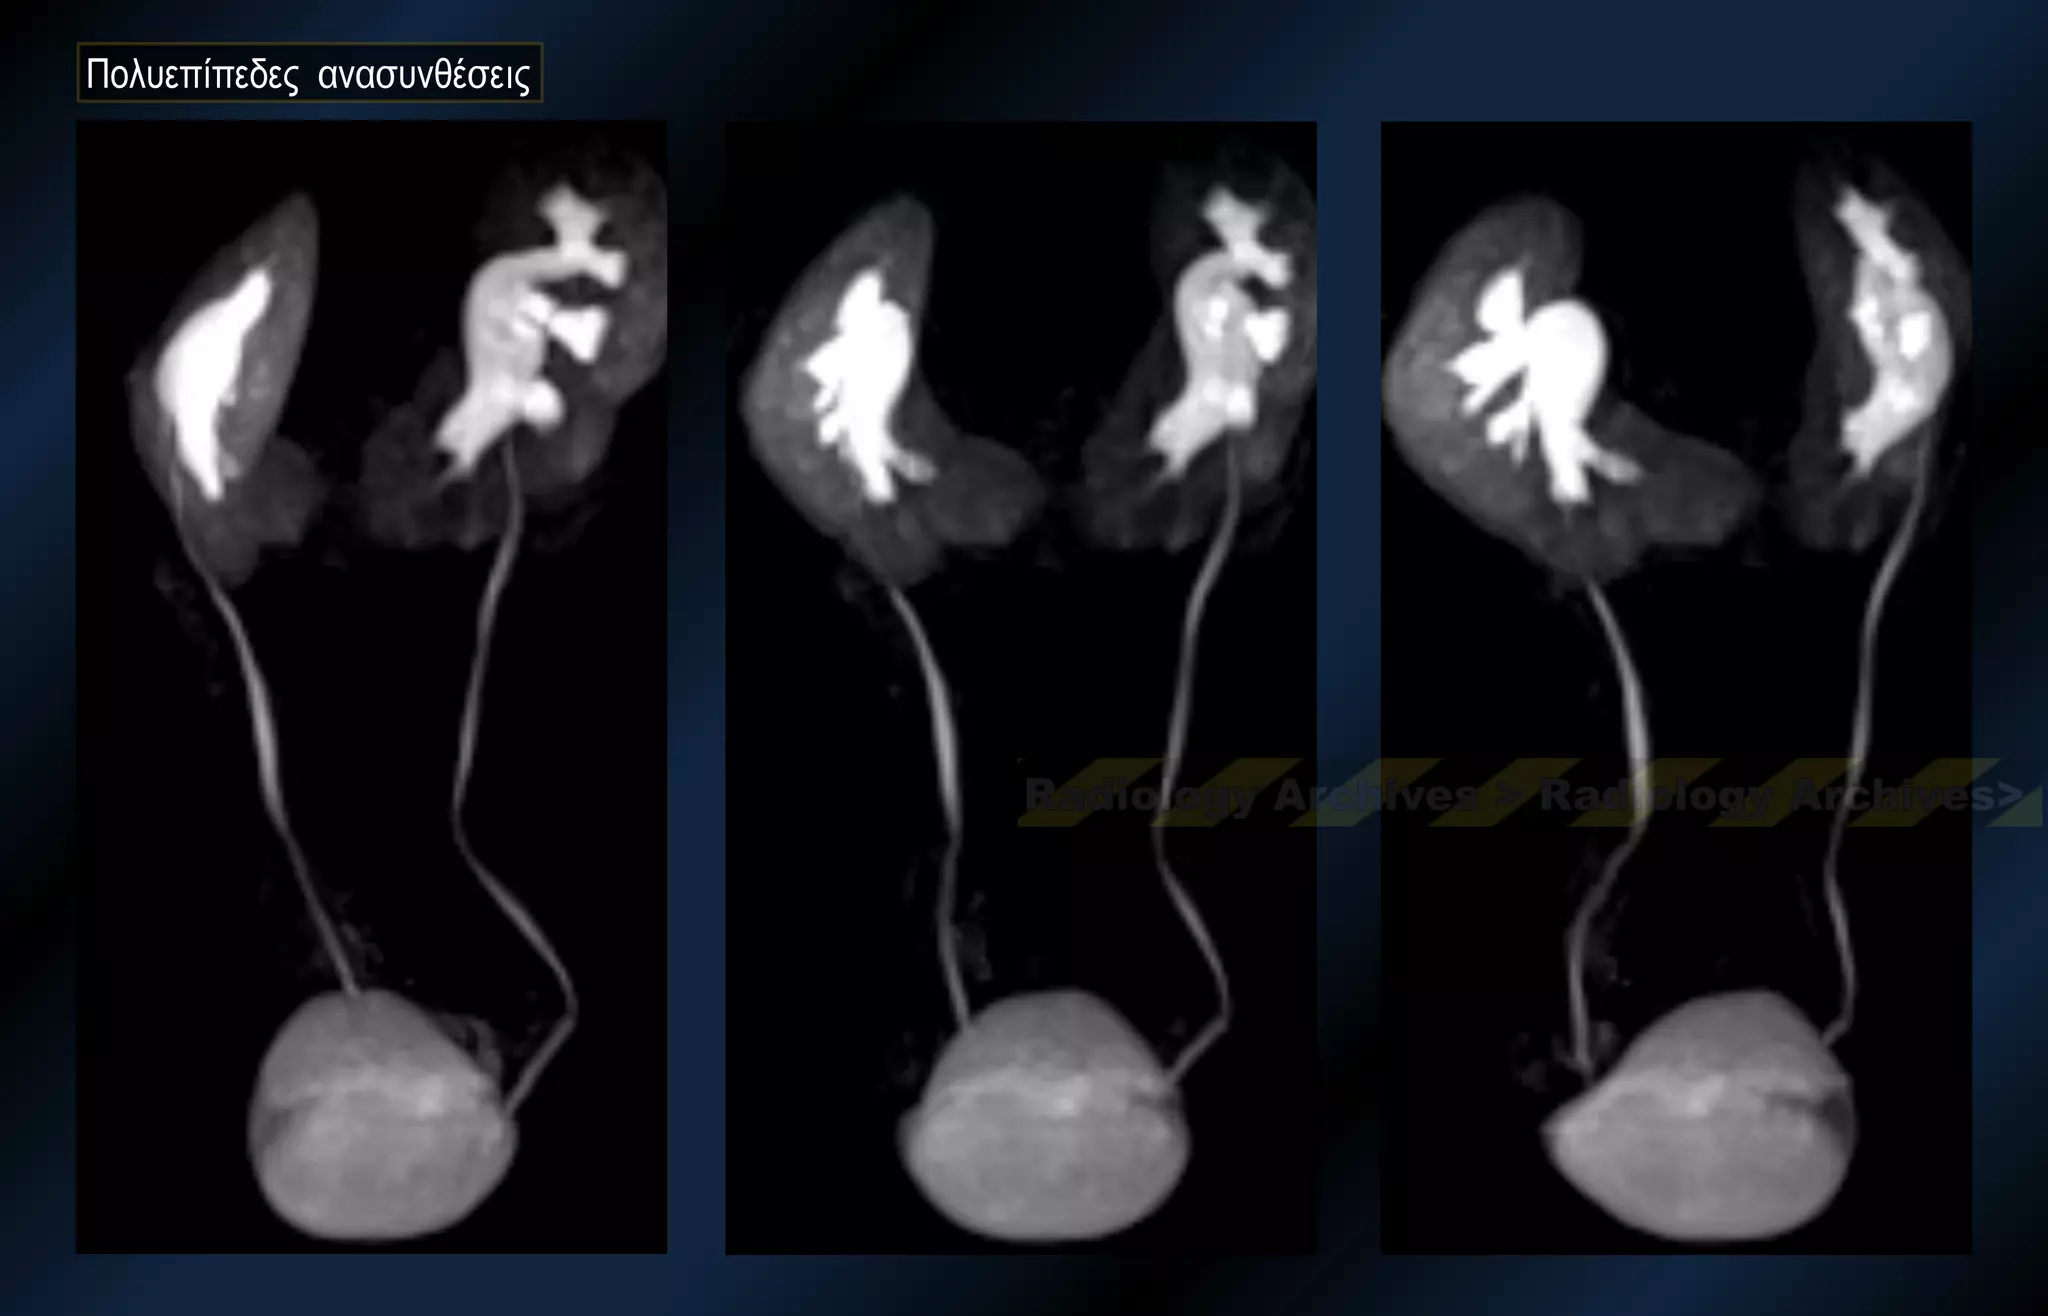

Πολυεπίπεδες ανασυνθέσεις

Άνδρας 38 ετών με κωλικό (ΑΡ) Νεφρού. Γνώστη η συγγενής ανωμαλία

Γυναίκα 48 ετώνσε τυχαίο έλεγχο προ γυναικολογικής επεμβασης. Πρωτοδιαγνωσθής ΠΝ Άνδρας 38 ετών με κωλικό (ΑΡ) Νεφρού. Γνώστη η συγγενής ανωμαλία